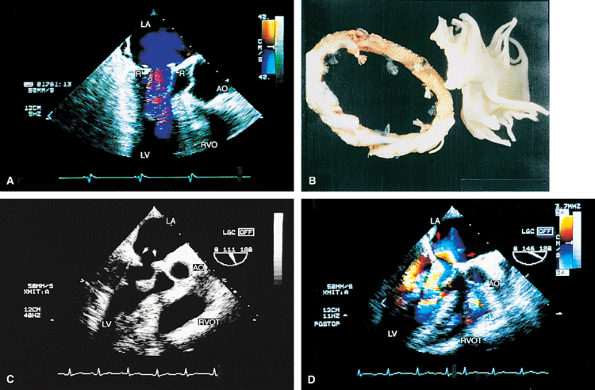

FIGURE 5.11. Starr-Edwards mitral prosthesis: dehiscence. The poppet, or ball (B), is seen in the closed (A) and open (B) positions. Note the reverberations from the ball partially obscuring the left ventricle (LV) in B. C,D. Eccentric, severe paravalvular mitral regurgitation (arrowheads) originating beyond the prosthetic (P) elements is shown. E.Color M-mode examination demonstrates systolic backflow (arrowheads) in the left upper pulmonary vein (LUPV), confirming the presence of severe MR. C, C, mitral ring. F. Gross specimen shows suture dehiscence and clot involving a Starr-Edwards prosthesis. AO, aorta; LA, left atrium; RA, right atrium; RV, right ventricle. |

|

FIGURE 5.12. Mitral annuloplasty rings. A. R points to the Carpentier ring in the mitral position. There is no obstruction to mitral flow. B. Gross specimen of Carpentier ring.C,D. Duran ring in the mitral position (arrows in C). D. Color Doppler examination shows prominent flow acceleration and aliased flow resulting from narrowing of the mitral orifice by the ring. AO, aorta; LA, left atrium; LV, left ventricle; RVO, RVOT, right ventricular outflow tract. |